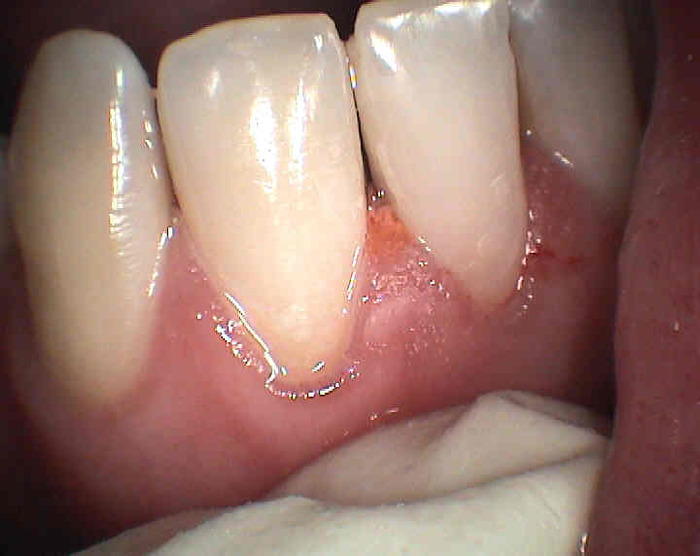

Zubní kaz (caries) je onemocnění způsobené ústní bakteriální flórou a charakterizované rozpadem zubních tkání. Vznikne tehdy, když jsou přítomny zbytky potravy a mikrobi (tedy zubní plak). Nejčastěji vzniká na místech nejhůře přístupných očistě tj. boční stěny zubů ohraničující mezizubní prostor (význam čištění mezizubí !), v rýhách na povrchu zubů, ale také na obnažených zubních kořenech nekrytých sklovinou (zubovina je ke kazu náchylnější z důvodu nižší mineralizace a vyššího obsahu organické hmoty) a na okrajích starých netěsnících výplní.

Příznaky zubního kazu : zdrsnění povrchu zubu, ulpívání zbytků potravy, bolestivost na podráždění (chlad, sladké, někdy při skusu), v mezizubním prostoru se může trhat zubní nit ( ostré okraje kazivé dutiny).